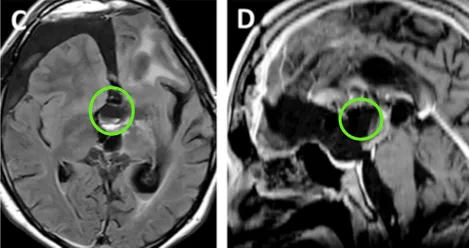

术前情况:MRI显示鞍区与丘脑存在巨大肿瘤,归类为Bcentral病变的复发性毛细胞星形细胞瘤,侵犯左侧海马旁回及侧脑室上部。肿瘤体积68.1 mm³,深度44.4 mm,侧面角21.9°。

术后情况:术后MRI显示肿瘤近全切,双侧大脑前动脉A2段灌注正常,视交叉、视神经束、垂体柄及下丘脑结构保全。